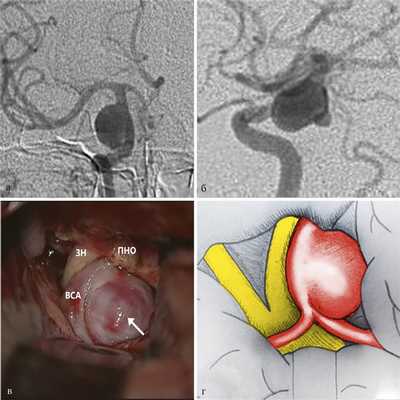

Латеральные аневризмы. Латеральные параклиноидные аневризмы встречаются в 16% случаев среди всех больших и гигантских аневризм ВСА [2]. Такие аневризмы смещают ВСА кпереди и куполом прилежат к ПНО. В связи с тем что ПНО достаточно ригидная структура, по мере увеличения тело латеральных параклиноидных аневризм смещается в супраклиноидное пространство и может достигать глазодвигательного нерва и базальных отделов височной доли. Ветви ВСА (ПВА и ЗСА) могут быть смещены и прижаты кверху. В ряде случаев при больших латеральных параклиноидных аневризмах после резекции ПНО удается достичь интракраниального, проксимального по отношению к аневризме, контроля ВСА. Клипировать такие аневризмы необходимо стандартными клипсами вдоль заднелатеральной стенки ВСА с сохранением устьев ЗСА и ПВА (рис. 6).

Рис. 6. Параклиноидная аневризма латерального расположения. а — ЦАГ, прямая проекция; б — ЦАГ, боковая проекция; в — операционный вид (ЗН — зрительный нерв, ПНО — передний наклоненный отросток, ВСА — внутренняя сонная артерия, стрелкой обозначено тело аневризмы); г — схема операционной картины: купол аневризмы направлен латерально, ВСА смещена кпереди.